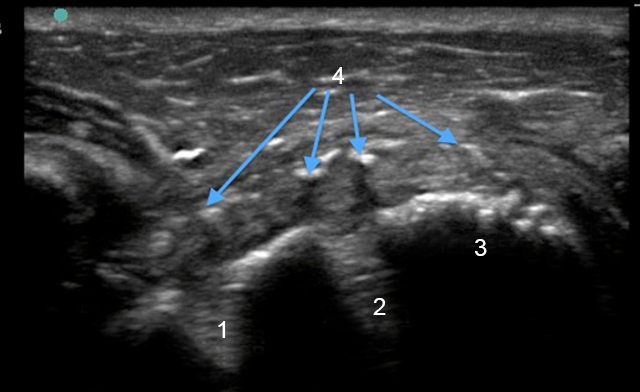

Shoulder Rotator Cuff Post-Operative Transverse Image

Anchor

Humeral Head

Suture